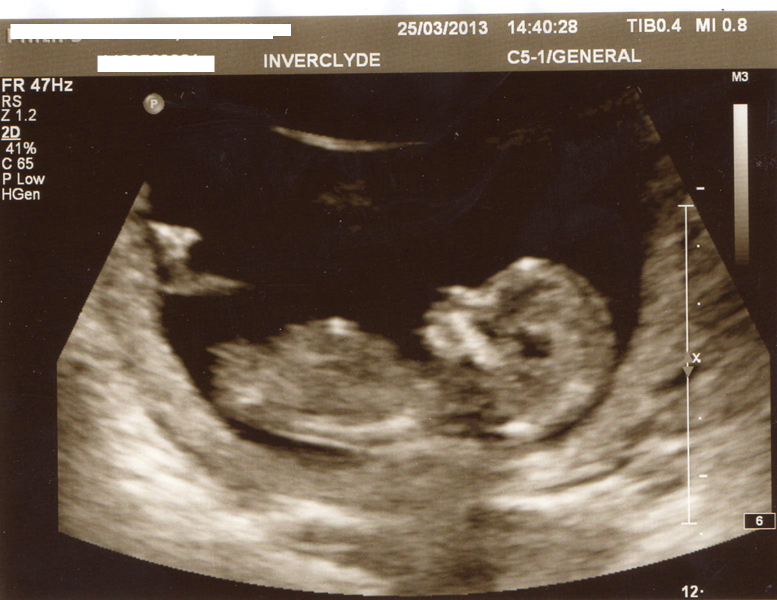

Hello. New here :) Looking for some help in predicting what my next little bundle will be. I have three boys and two girl. Scan was taken at 13+2. Thank you in advance.

Attachment 10562

Thinking pink maybe :)

I don't think we're seeing the whole nub.